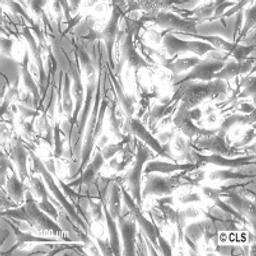

Human Skin melanoma cell line SK-MEL-28

Morphology: Polygonal

Growth Properties: Monolayer, adherent